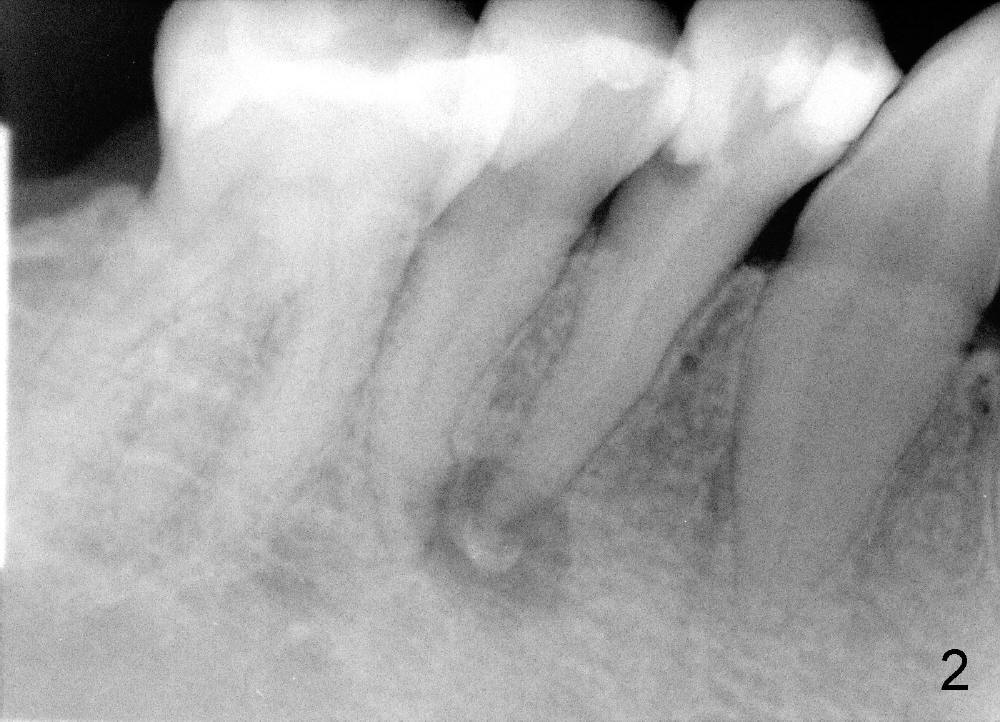

言归正传,五十一岁女人昨天第一次来诊所就诊(急诊),去年十一月在别的诊所右下第一双尖牙远中做树脂修复,术中发现穿髓,术后不时,现在颊侧根尖有压痛,根尖片显示根尖阴影(图一),多谢田智敏几天前指导,现在看根尖片,多注意些根尖弯曲,根管治疗中,不由自主地事先弯曲细小根管锉(hand files),一点没有问题,一直使用到二十号根管锉,根管长度21.5毫米(working length (WL)),下颌第一双尖牙一般单根,属于大根(方老师见解),接着用40/.06 rotary file(用了几年rotary files,大多数根管治疗好像不需要按部就班地使用crown down 技术:例如先用40/.10 rotary file,然后40/.08, 再用40/.06),问题在于这个rotary file只能进入十七毫米,突然在梦中清醒:根管是弯曲的。由于急诊时间紧,接着使用30/.04 rotary file,能达到WL,然后让漂白液浸泡根管十到二十分钟,去处理另外一个病人。回来后用30/.06 rotary file也没有问题,反复冲洗后,吸干根管,放置Ca(OH)2糊剂(图二:超冲些)。如果下次病人回来时没有疼痛症状,冲洗掉Ca(OH)2糊剂,便使用30/.06主牙胶尖充填,重新做树脂修复(老的有leakage),如果新的树脂没有leakage(拍摄X光片),我可能同意病人意见:不做牙冠。仿佛这例牙冠必要性不大。方老师,田兄,或者任何人:您们怎么处理这样病例?图三是以前拍摄的全景片,显示左下第二双尖牙根尖够弯曲的。